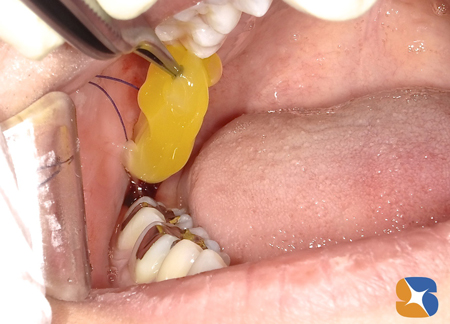

静脈麻酔鎮静法を使っての抜歯を行いました。

歯茎を開くと、下顎の骨の中に完全に包囲されている親知らずの歯を確認することが出来ました。

左右の抜歯に合計2時間ほどの時間を要したため、最後の方は鎮静麻酔からも覚めてきていました。抜歯跡にフィブリンの塊を何層も埋めてから、糸を縫いました。